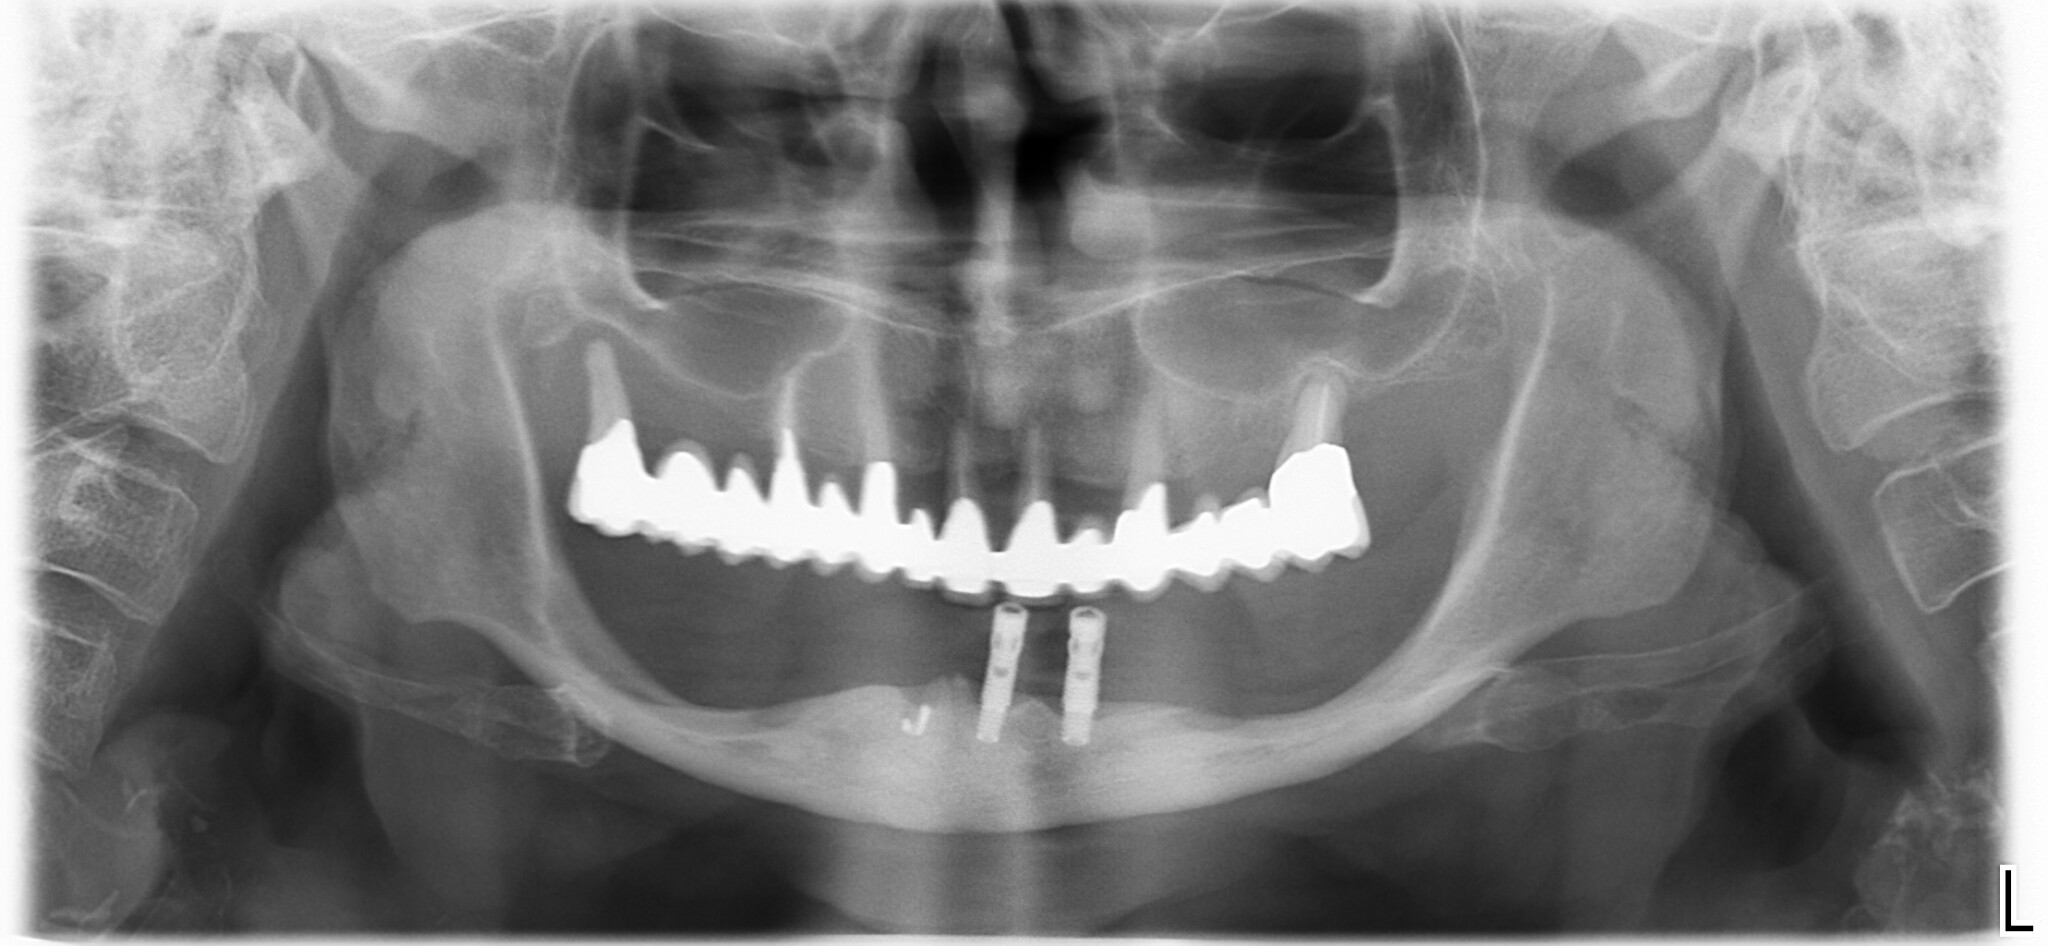

Per fare un esempio, già nel 2012 l’ EAO, dichiarava che non sembra esserci motivo per inserire più di 4 o 6 impianti nella riabilitazione di un’arcata e che il trattamento con 4 impianti era, già allora, una soluzione ben documentata… ergo non c’è motivo di mettere più di 4 impianti. Quindi la riabilitazione di una mandibola edentula sarà un all-on-4, sempre e comunque… a meno che non ci siano controindicazioni assolute all’implantologia le quali comprendono anche, ovviamente, la non solvibilità economica.

Tutto ciò, mi dispiace, non ha alcuna influenza sul trattamento ottimale che resta, appunto: quattro impianti dritti intraforaminali con 12 denti avvitati sopra.

Ora che hai capito come la penso riguardo a (quasi) tutte le mandibole edentule del mondo penso sia arrivato il momento di dare un’occhiata al mio intervento di 5 anni fa che magari qualcuno potrà trovare utile… e sai una cosa? Oggi, 5 anni dopo, avrei fatto esattamente gli stessi movimenti… nello stesso ordine!